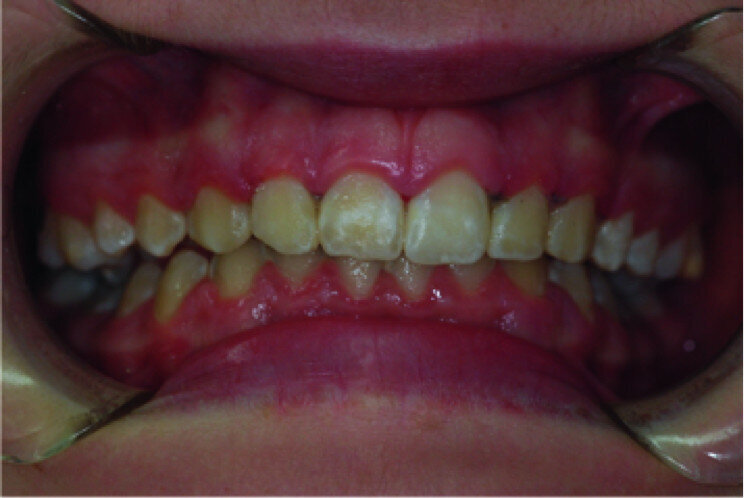

Application of a topical anaesthetic.

A 14-year-old female patient was referred to our department by the orthodontics unit because, at the end of fixed orthodontic treatment, she had developed gingival enlargement in the upper arch (Fig. 1), probably related to the fast closure of the spaces associated with very poor oral hygiene due to bleeding during toothbrushing. Just after the removal of the appliance, a topical anaesthetic (EMLA, AstraZeneca) was applied to the gingivae (Fig. 2) and a gingivectomy was performed using a diode laser (XD-2, Fotona) according to the technique of removal of the inter dental papillae (Fig. 3). The parameters used were as follows: a wavelength of 808 nm, 3 W in continuous wave, a 320 μm fibre in contact mode. The intervention had a duration of 375 seconds, and the patient did not feel any pain (Fig. 4). After the intervention, the patient did not take any kind of pain medication, and the healing process was completed in five days (Fig. 5).